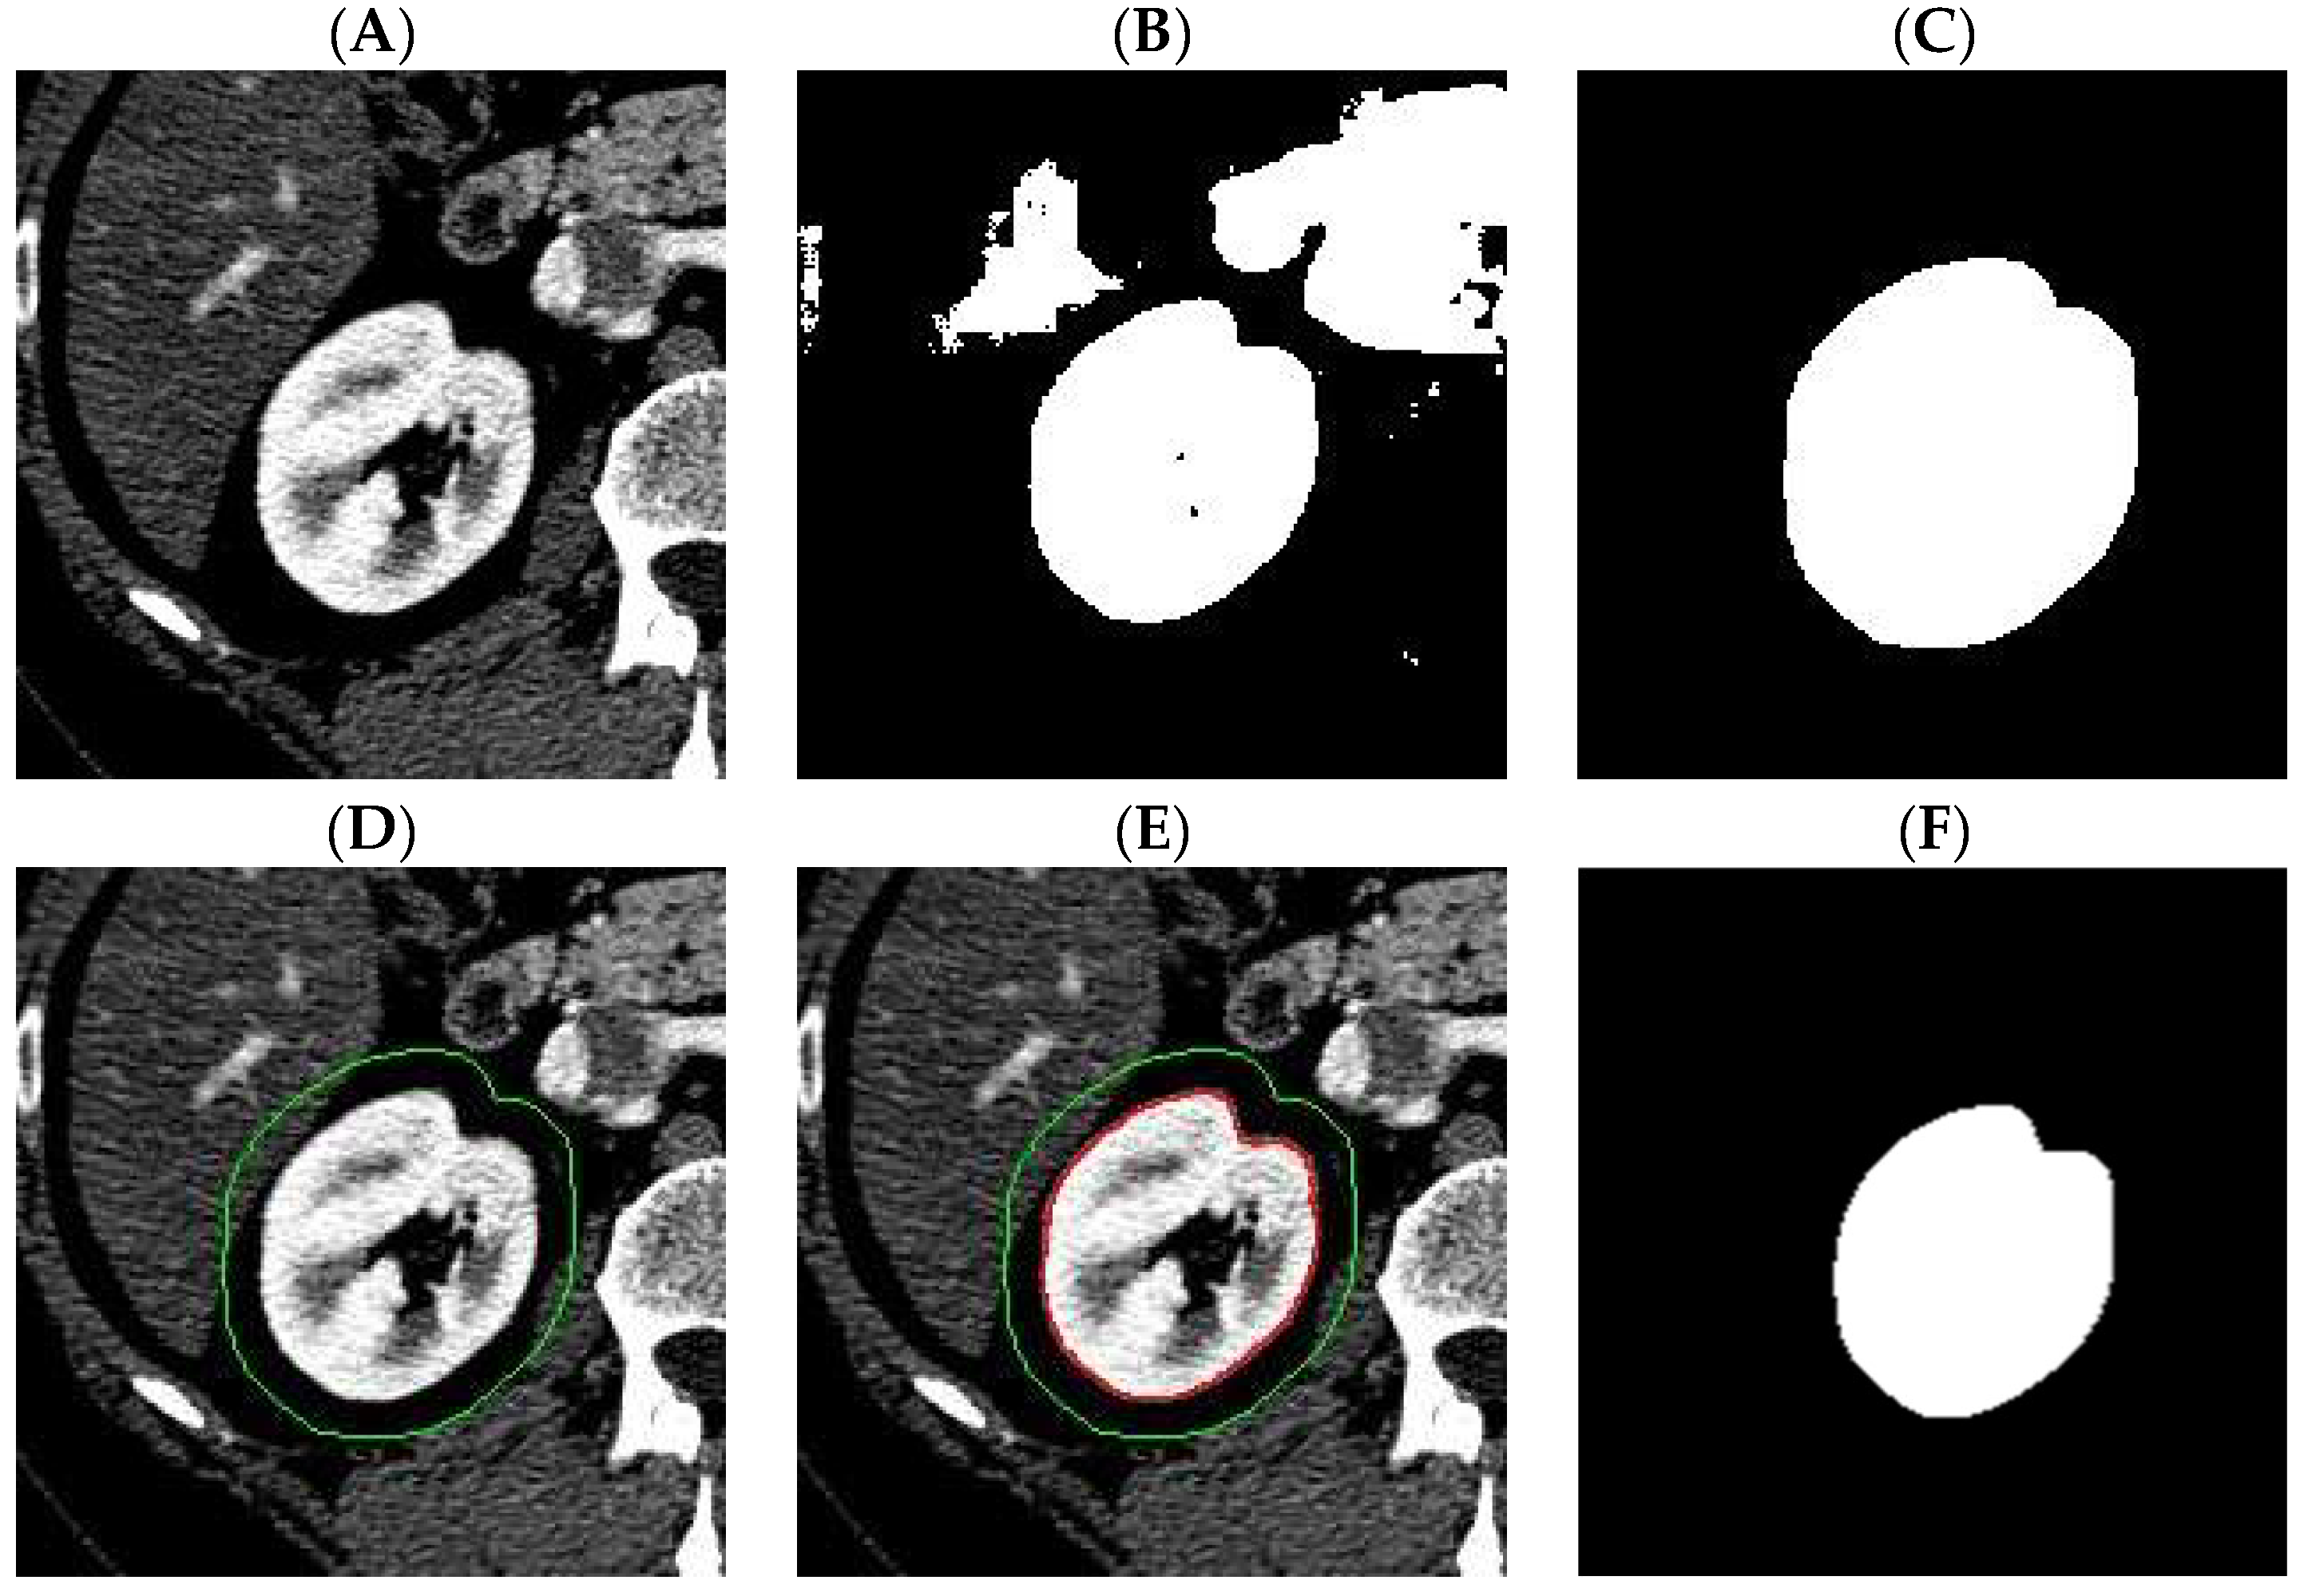

Figure 7 shows the visualization of the results in the individual steps of the algorithm.

Figure 7. Visualization of the results in individual steps of the algorithm. (A): Raw image, (B): Image after applying U-Net without morphological transformations, (C): Image after initial morphological transformations (progression, holes filling), (D): Original image with starting search area ( S m ), (E): Image after applying extended maxima transformation (red border), (F): Reference mask manually generated by a human expert.